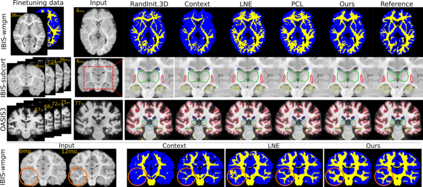

Recent self-supervised advances in medical computer vision exploit global and local anatomical self-similarity for pretraining prior to downstream tasks such as segmentation. However, current methods assume i.i.d. image acquisition, which is invalid in clinical study designs where follow-up longitudinal scans track subject-specific temporal changes. Further, existing self-supervised methods for medically-relevant image-to-image architectures exploit only spatial or temporal self-similarity and only do so via a loss applied at a single image-scale, with naive multi-scale spatiotemporal extensions collapsing to degenerate solutions. To these ends, this paper makes two contributions: (1) It presents a local and multi-scale spatiotemporal representation learning method for image-to-image architectures trained on longitudinal images. It exploits the spatiotemporal self-similarity of learned multi-scale intra-subject features for pretraining and develops several feature-wise regularizations that avoid collapsed identity representations; (2) During finetuning, it proposes a surprisingly simple self-supervised segmentation consistency regularization to exploit intra-subject correlation. Benchmarked in the one-shot segmentation setting, the proposed framework outperforms both well-tuned randomly-initialized baselines and current self-supervised techniques designed for both i.i.d. and longitudinal datasets. These improvements are demonstrated across both longitudinal neurodegenerative adult MRI and developing infant brain MRI and yield both higher performance and longitudinal consistency.